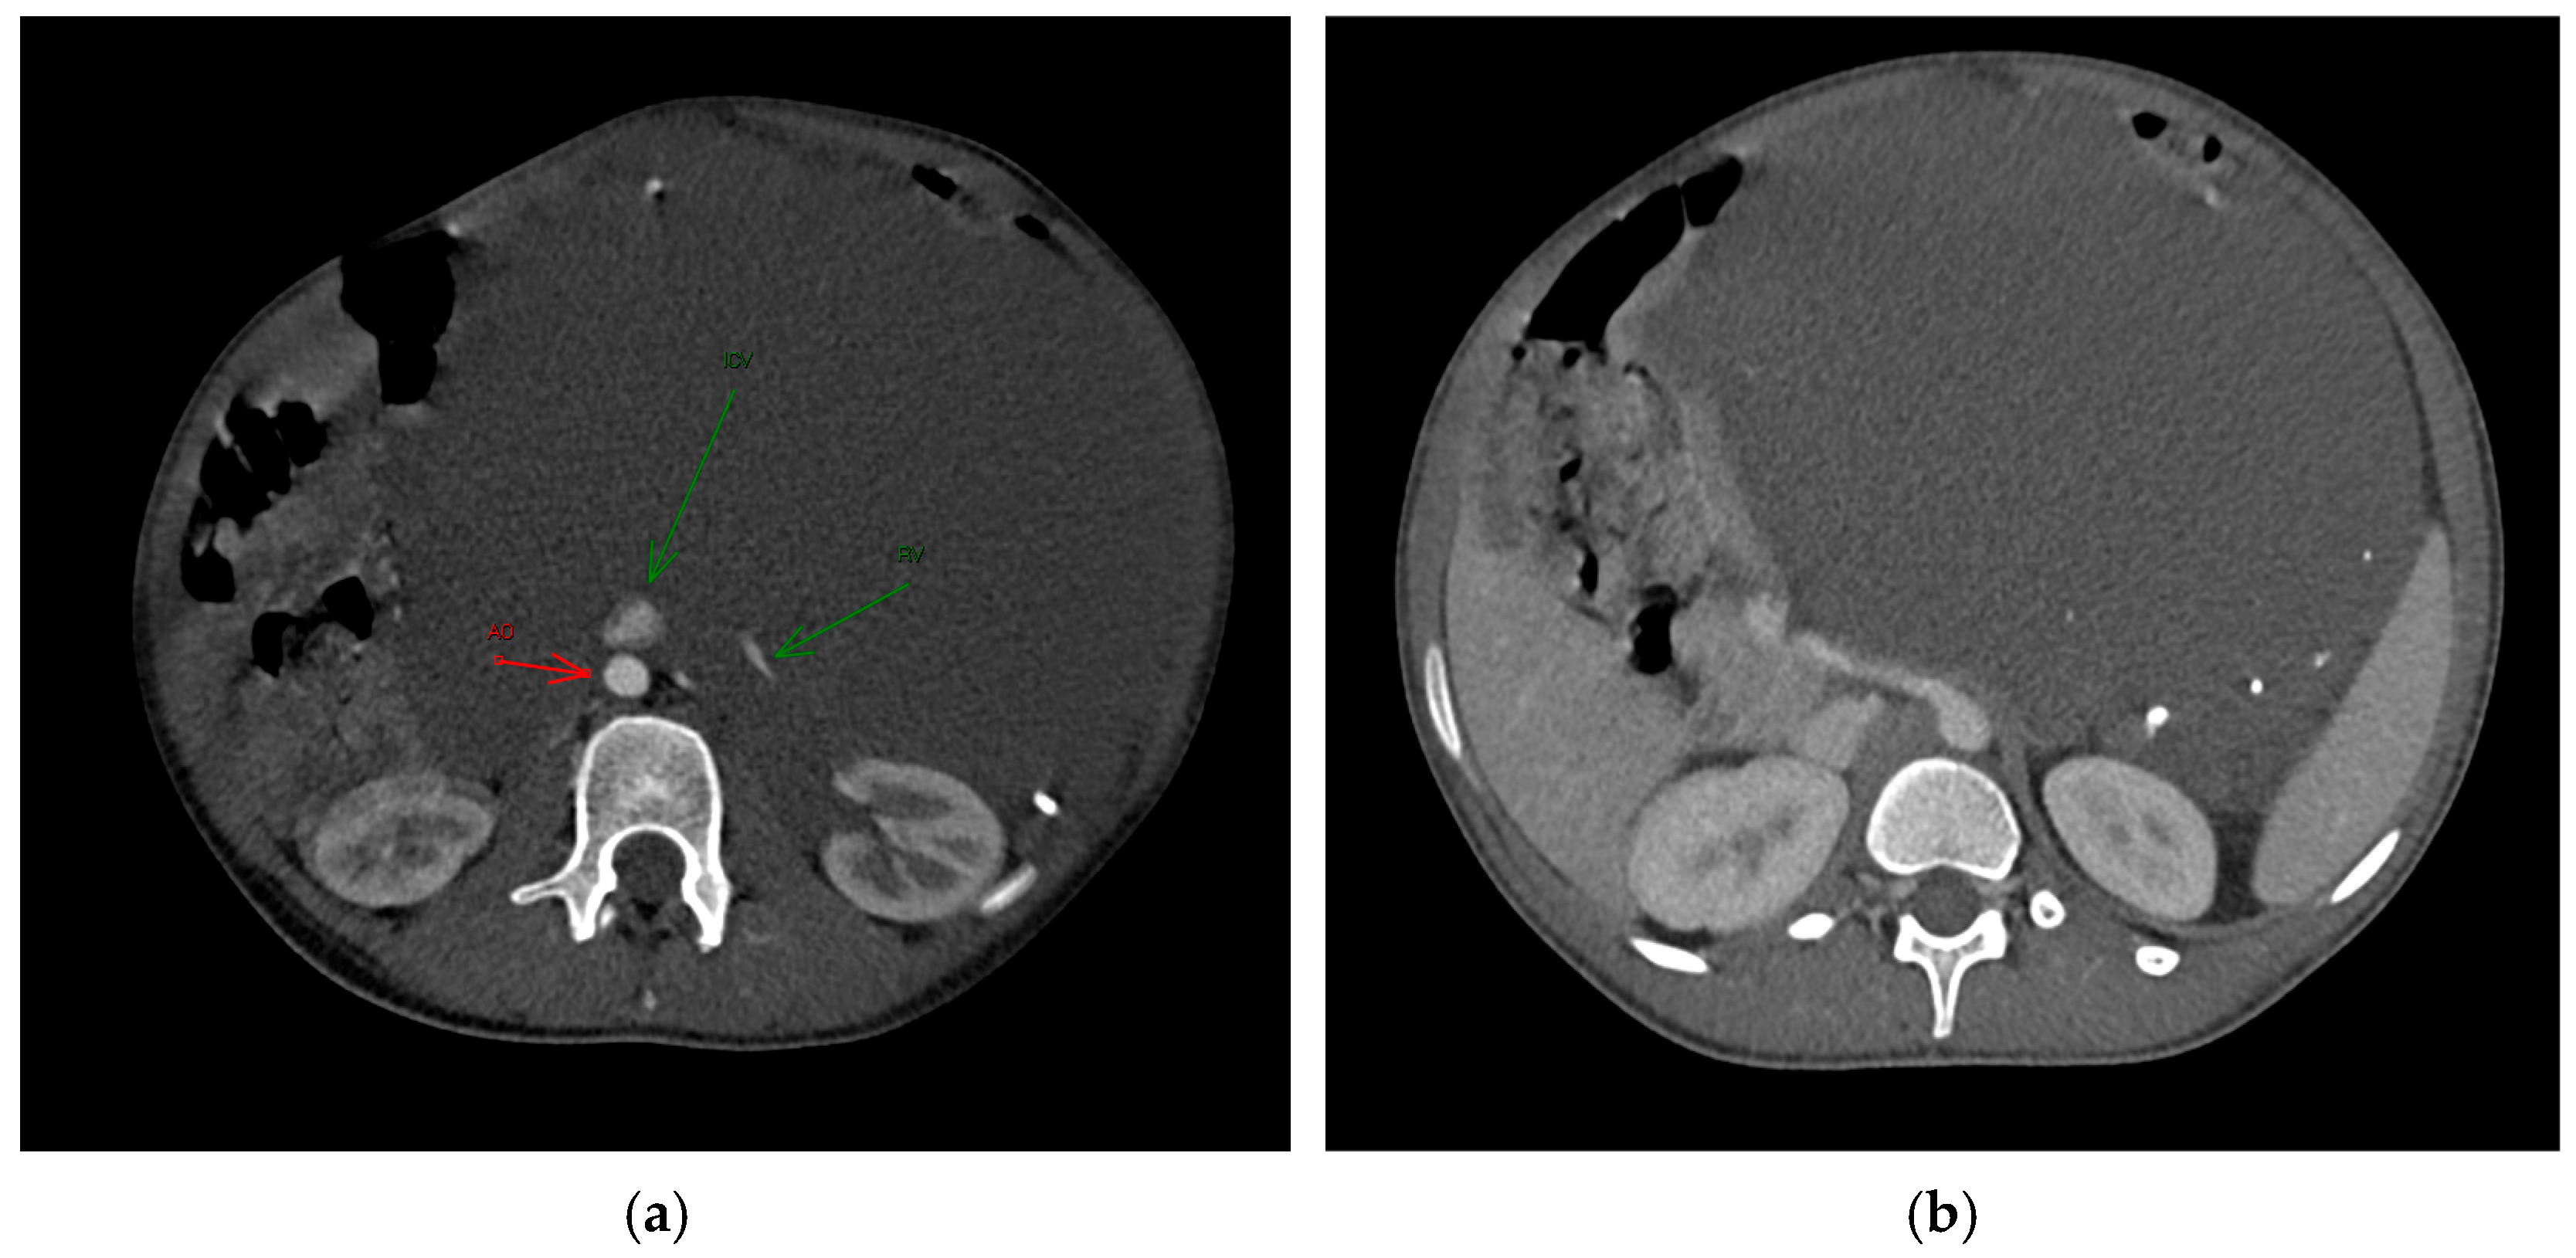

Figure 1. The axial post-contrast CT in the arterious (a) and portovenous (b) phase reveals the full extent of the mass and its intra-peritoneal location, without infiltration of the adjacent structures. The mass contains calcified density components, which were later identified as phleboliths. (a): Green arrows indicated the Renal Vein (RV) and Inferior Vena Cava (ICV); red arrow indicated the Aorta (AO).

An ultrasound examination was performed with the visualization of a multiloculated lesion, characterized by anechoic and hypoechoic cystic spaces separated by thin septations, with moderate intralesional vascularization observed after color Doppler evaluation. Then, a second-level imaging with contrast-enhanced CT scan of the abdomen was performed, revealing an intraperitoneal large, multiseptated hypodense mass containing multiple calcified components (Figure 1), measuring approximately 21 × 16 cm in the axial plane and extending up to 30 cm in the sagittal plane. The lesion occupied nearly the entire abdominal cavity, predominantly on the left side, compressing adjacent structures. It wrapped smoothly around the left kidney and adrenal gland, displacing bowel loops and other abdominal organs, with a poorly defined interface with the surrounding tissues.

The major abdominal vessels, including the celiac trunk, superior mesenteric artery, inferior mesenteric artery, and the inferior vena cava, as well as both renal veins and arteries, were compressed with a partial course within the mass itself. However, no evidence of vascular compromise was observed.